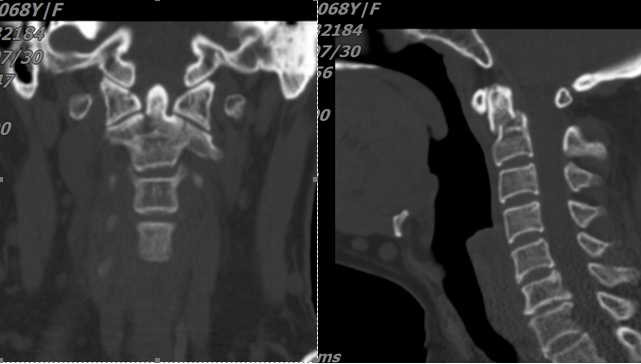

图一:颈椎齿状突骨折、骨折移位伴寰枢椎脱位

图二:颈椎齿状突骨折,骨折线前下往后上,属于IIC型

寰枢椎在人体结构中占有极为重要的地位,被称作“生命禁区”。首先是因为,寰椎属于颈颅交界区,此处有椎动脉和重要的生命中枢——延髓。其次,椎板间有粗大的静脉丛、枕大神经,解剖结构复杂,手术难度大、风险高,一旦发生意外会直接危及生命。再次,寰椎后弓进钉点高度平均约4mm,而现在医用螺钉直径为3.5mm。最重要的是,以往的寰枢椎固定是在相对稳定的骨质上操作。本例手术需要在不稳定的寰枢椎上钻孔置钉。这些对手术的开展都是巨大的考验。